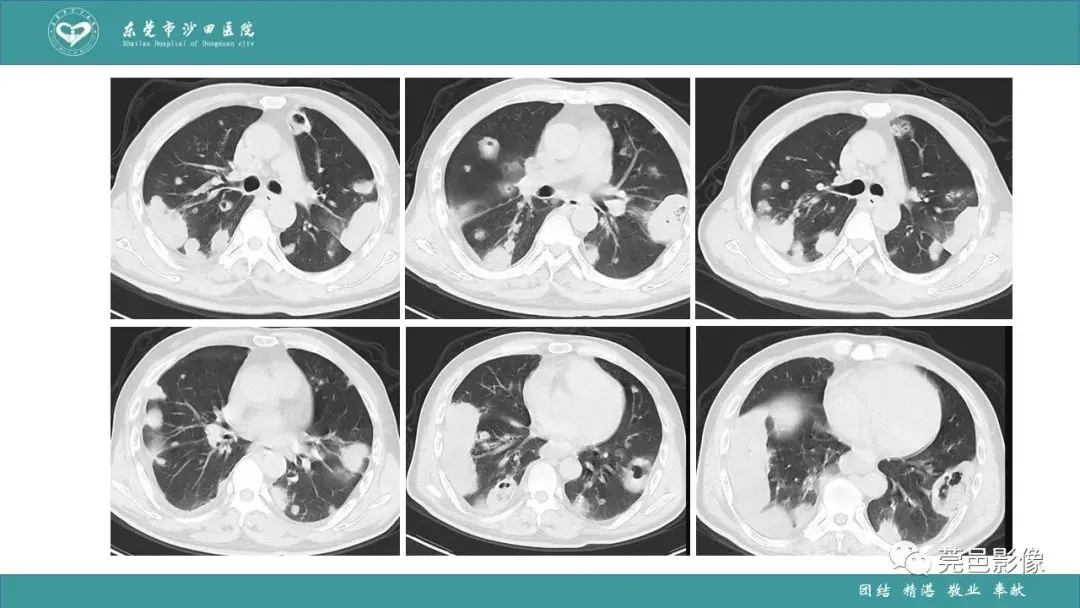

>课件 | 肺炎克雷伯杆菌肺炎影像学诊断与鉴别诊断

课件 | 肺炎克雷伯杆菌肺炎影像学诊断与鉴别诊断